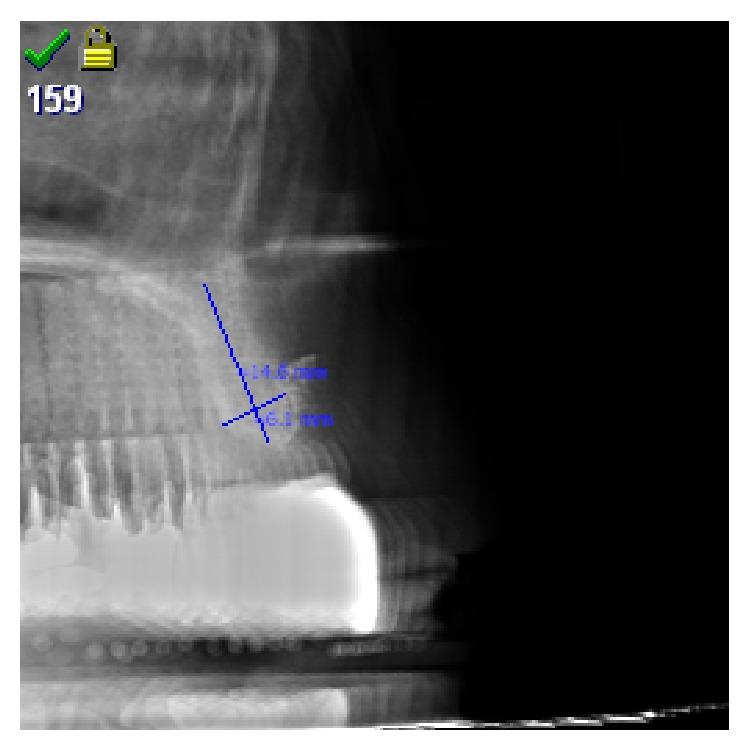

82 patients with horizontal atrophy of anterior maxillary crest were treated with PeSPTT and randomly assigned biphasic (60% HA/40% bTCP) or monophasic (100% bTCP) SHB without or with addition of aPRF. 109 implants were inserted into the augmented sites after 8.3 months and the insertion-torque-value (ITV) measured as clinical expression of the (bio)mechanical stability of the augmented bone and compared to ITVs of a prior study in sinus lifting.

82例上颌前牙嵴水平萎缩患者接受了PeSPTT治疗,并随机分配使用双相(60% HA/40% bTCP)或单相(100% bTCP)SHB,且添加或不添加aPRF。8.3个月后,将109颗种植体植入植骨部位,并测量植入扭矩值(ITV),作为植骨部位(生物)力学稳定性的临床指标,并与之前一项上颌窦提升研究中的ITV进行比较。